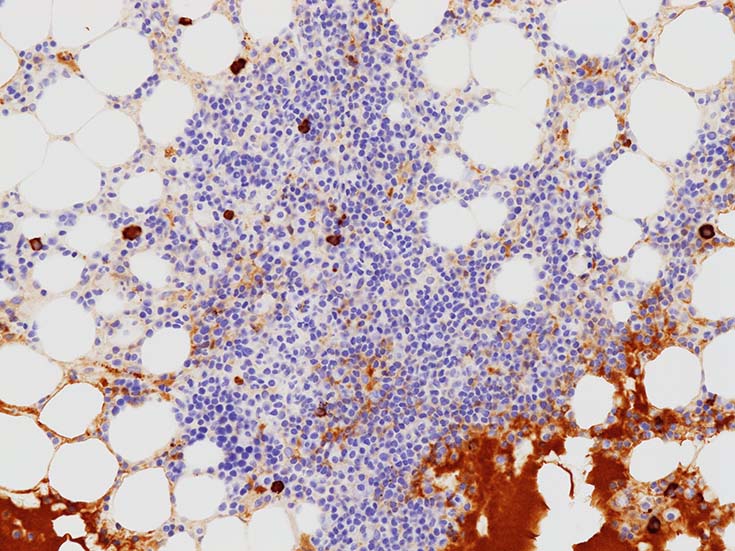

増殖するB細胞はCD19+, CD20+. 結節内に増加する形質細胞はCD19+, CD20‐である. (多発性骨髄腫の形質細胞様細胞はCD19陰性).~  多くのB細胞がMUM1陽性を示す. CD5, CD10, BCL6は陰性.

CD138陽性形質細胞の分布. 中央部よりも周辺部に陽性細胞が多くみられる.

light chain, kappa/ lambda-ISHでは, kappa>lmbdaであるが, この結果より, 明瞭なrestrictionと断定するのは難しい.

通常/ 正常の骨髄クロットでは 背景タンパク液のIgMはそまらないかごく淡い陽性. しっかり陽性を示す本例では血中IgMの増加を示唆する. IgMに染まる形質細胞が増加している.

多発性骨髄腫などと違い, 他の免疫グロブリンが強く抑制されることは少ないようである.